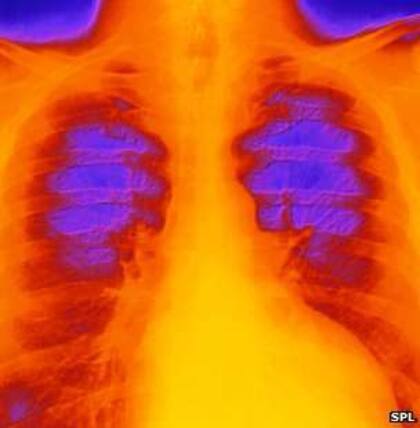

Algunas personas hablan de "síndrome de corazón roto", conocido más formalmente como cardiomiopatía por estrés o cardiomiopatía takotsubo.

"Es una condición temporal en la que el músculo cardíaco se debilita repentinamente o se aturde. El ventrículo izquierdo, una de las cavidades del corazón, cambia de forma", según explican en la Fundación Británica del Corazón.

El nombre científico, cardiomiopatía takotsubo proviene de la palabra japonesa usada para referirse a un tipo de trampa de fondo redondo y cuello estrecho usada para cazar pulpos. El estrés súbito hace que el ventrículo izquierdo del corazón -el que bombea la sangre- adquiera esta forma.